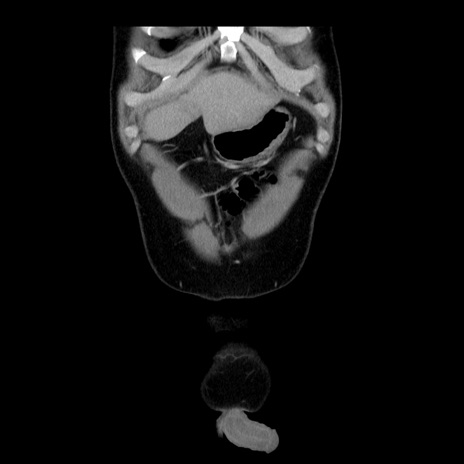

症例4(冠状断像)

【症例】30歳代男性

【主訴】腹痛、嘔吐

【現病歴】昨晩から突然の腹痛あり、その後嘔吐、軟便も出現。腹痛が改善しないため救急搬送となる。2日前にしめ鯖の食事歴あり。

【身体所見】意識清明、苦悶様、BP 135/90mmHg、BT 35.7℃、腹部:平坦、やや硬、心窩部〜臍部に自発痛、圧痛あり、筋性防御+、反跳痛-

【データ】WBC 8100、CRP 0.57